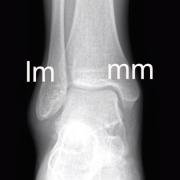

Because the ankle bones are part of the tibia and fibula, any deformity or stress in the ankle can directly influence the knee.